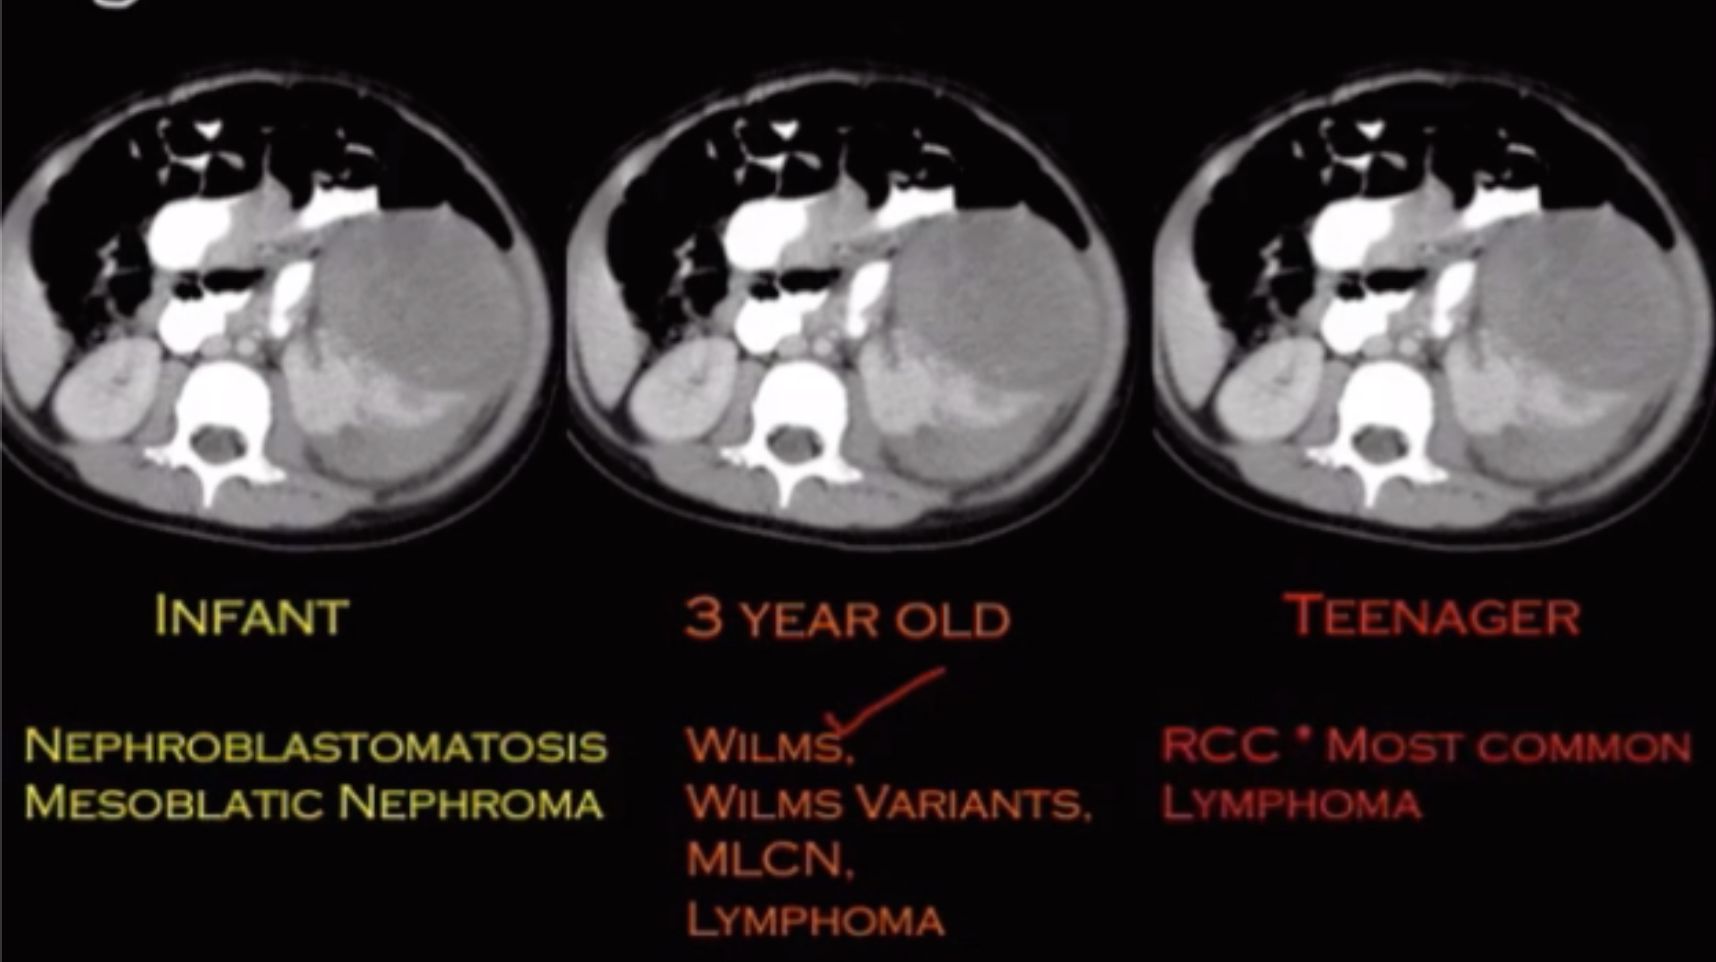

Wilms Tumor

• Rarely has calcifications

• Age ~4 yo (never seen before 2 months old)

• More commonly mets to lung & liver

• Does not invade spinal canal

• Retroperitoneal lymphadenopathy uncommon

• Claw sign

• Evaluate for renal/IVC thrombus or invasion

• Do not biopsy - will seed

Nephroblastomatosis

• Persistent nephrogenic rests (embryologic tissue that makes up the kidney)

• Looks like thick rhind around kidney (or like the renal cortex is severely thickened)

• Can be precursor to wilms tumors

• Found in all cases of bilateral wilms tumor

Multilocular Cystic Nephroma

• Michael Jackson disease

• Males 3 months - 5 years

• Middle aged women

• Multiloculated cystic mass

• Hemorrhage and necrosis uncommon

• DICER1 gene mutation

• 10% associated with pleuropulmonary blastoma

• Just looks like densely packed cysts together